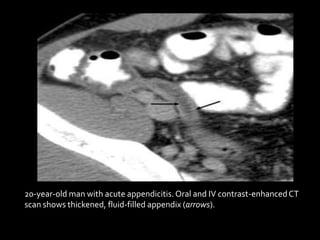

20-year-old man with acute appendicitis.Oral and IV contrast-enhancedCT

scan shows thickened, fluid-filled appendix (arrows).